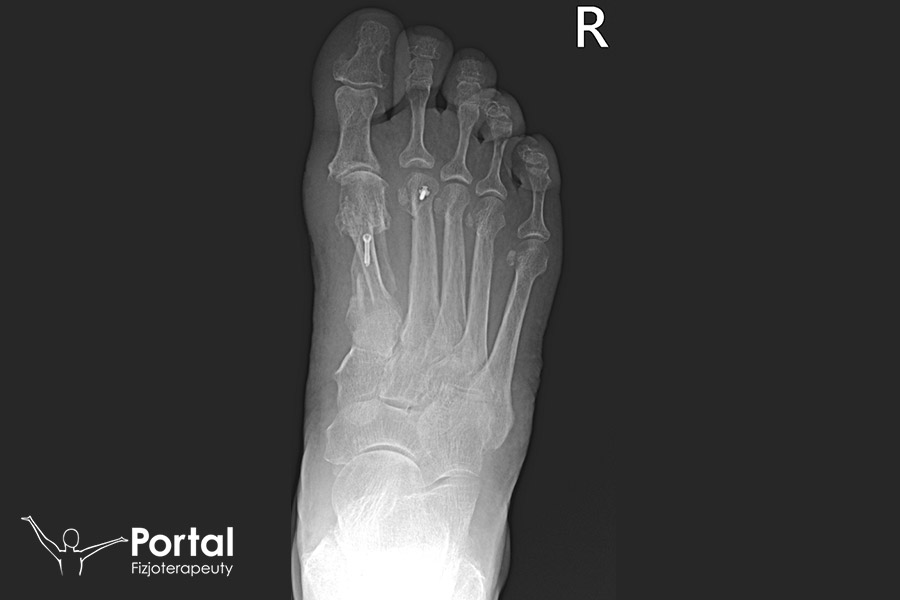

Osteotomia SCARF to operacja wykonywana w znieczuleniu przewodowym, czyli takim, w którym pacjent przestaje czuć swoje ciało od pasa w dół. Pozostaje jednak świadomy. Trwa około 30-60 minut. Celem zabiegu jest wykonanie podłużnego cięcia skóry wzdłuż przyśrodkowej powierzchni przodostopia, dzięki czemu chirurg zyskuje bardzo dobre pole widoczności. Cięcie przebiega dokładnie w płaszczyźnie horyzontalnej I kości śródstopia, po czym wykonuje się przesunięcie względem siebie uzyskanych w ten sposób „belek kostnych”. Po ustaleniu docelowej korekcji zniekształcenia dokonuje się zespolenia dwiema śrubami. Osteotomię poprzedza boczne uwolnienie stawu śródstopno-paliczkowego I oraz trzeszczek. Na zakończenie operacji nierzadko wymagana jest osteotomia Akina paliczka bliższego palucha uzupełniająca ostatecznie korekcję koślawości.

W przypadku niewystarczającej stabilności w płaszczyźnie strzałkowej konieczność użycia śruby można zniwelować poprzez założenie szwu kostnego. Efektem jest przywrócenie stopie estetyki i biomechaniki poprzez usunięcie deformacji nazywanej haluksem. Główne zalety metody to: znaczna stabilność zespolenia, możliwość trójpłaszczyznowej korekcji ustawienia I kości śródstopia i szybki powrót pacjentów do pełnego obciążania przodostopia.